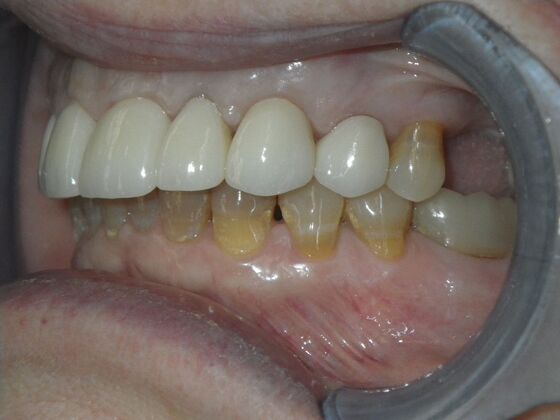

Cosmetic Changes with Veneers and Crown and Bridge: Case 1

Patient presented with spacing between upper central incisors and dark tetracycline stains that she wanted corrected